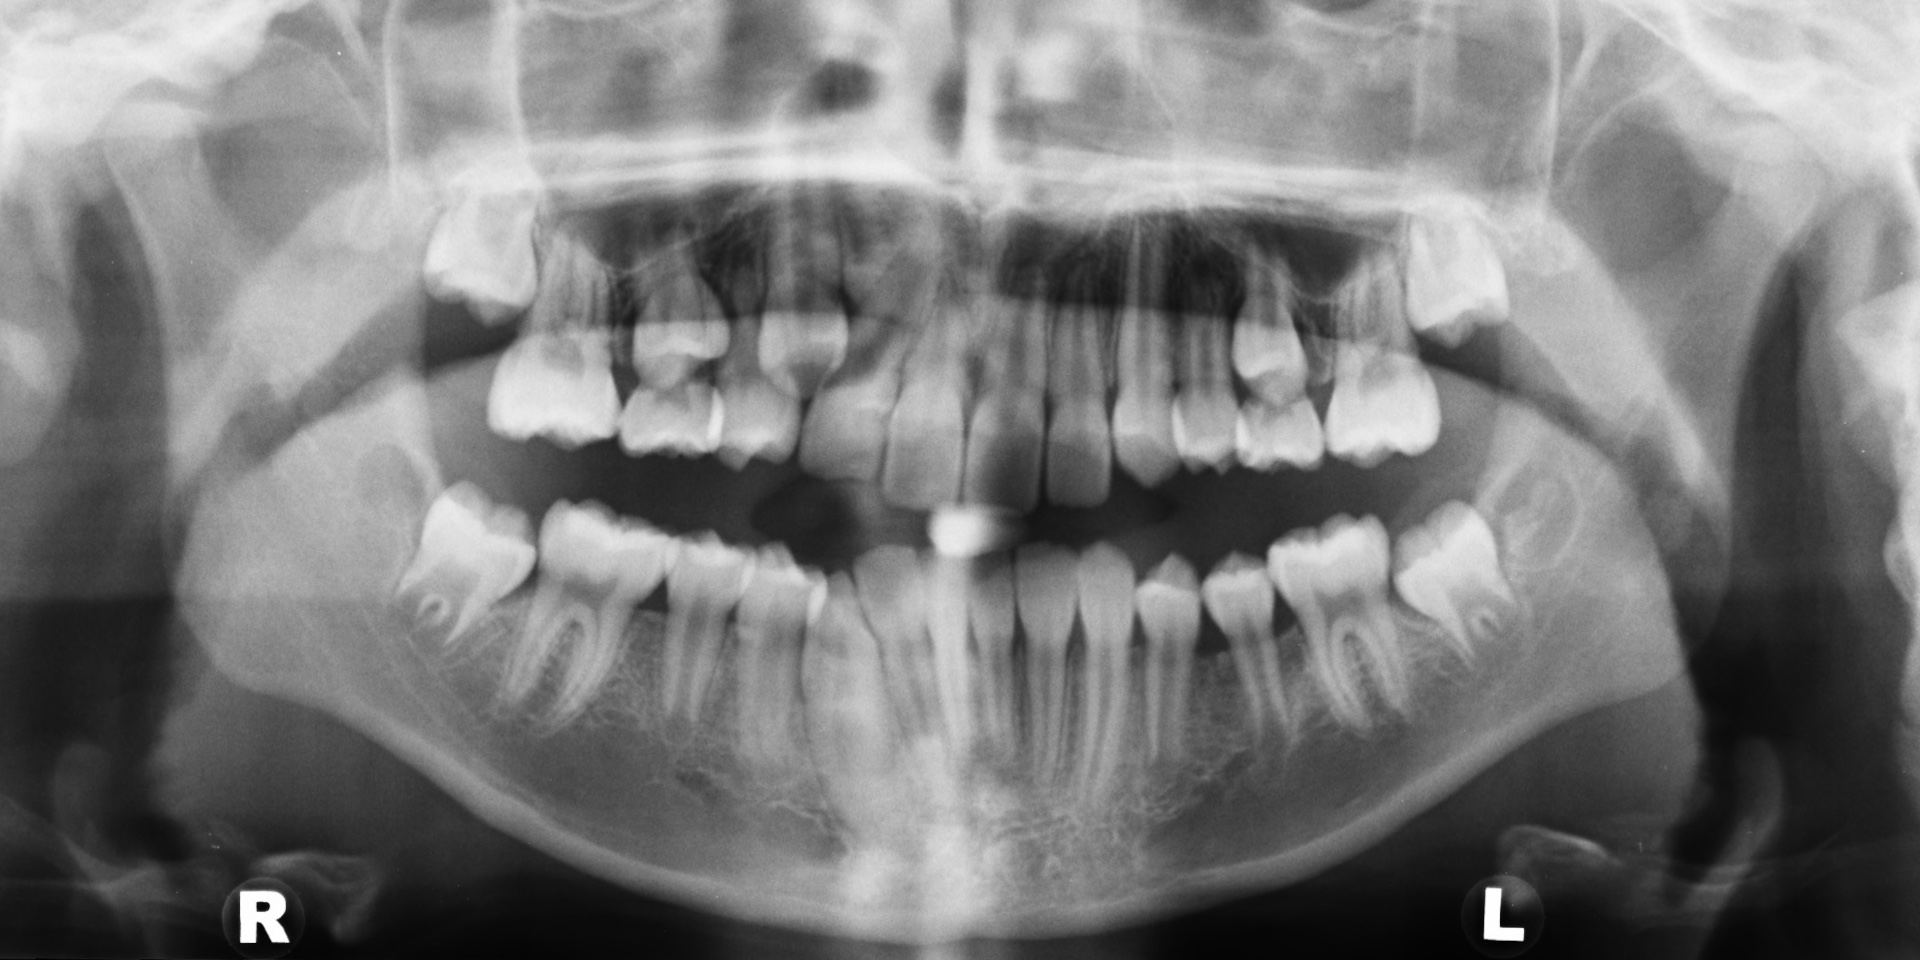

Lateral Cephalometric X-ray of the head

Orthopantomograph X-ray of the teeth and jaws